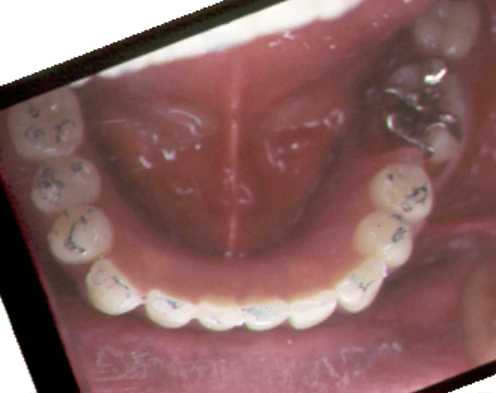

下顎オーバーデンチャー

1本を残して後は欠損

4本インプラント植立ごの支台

各支台を連結

その上に義歯をのせる